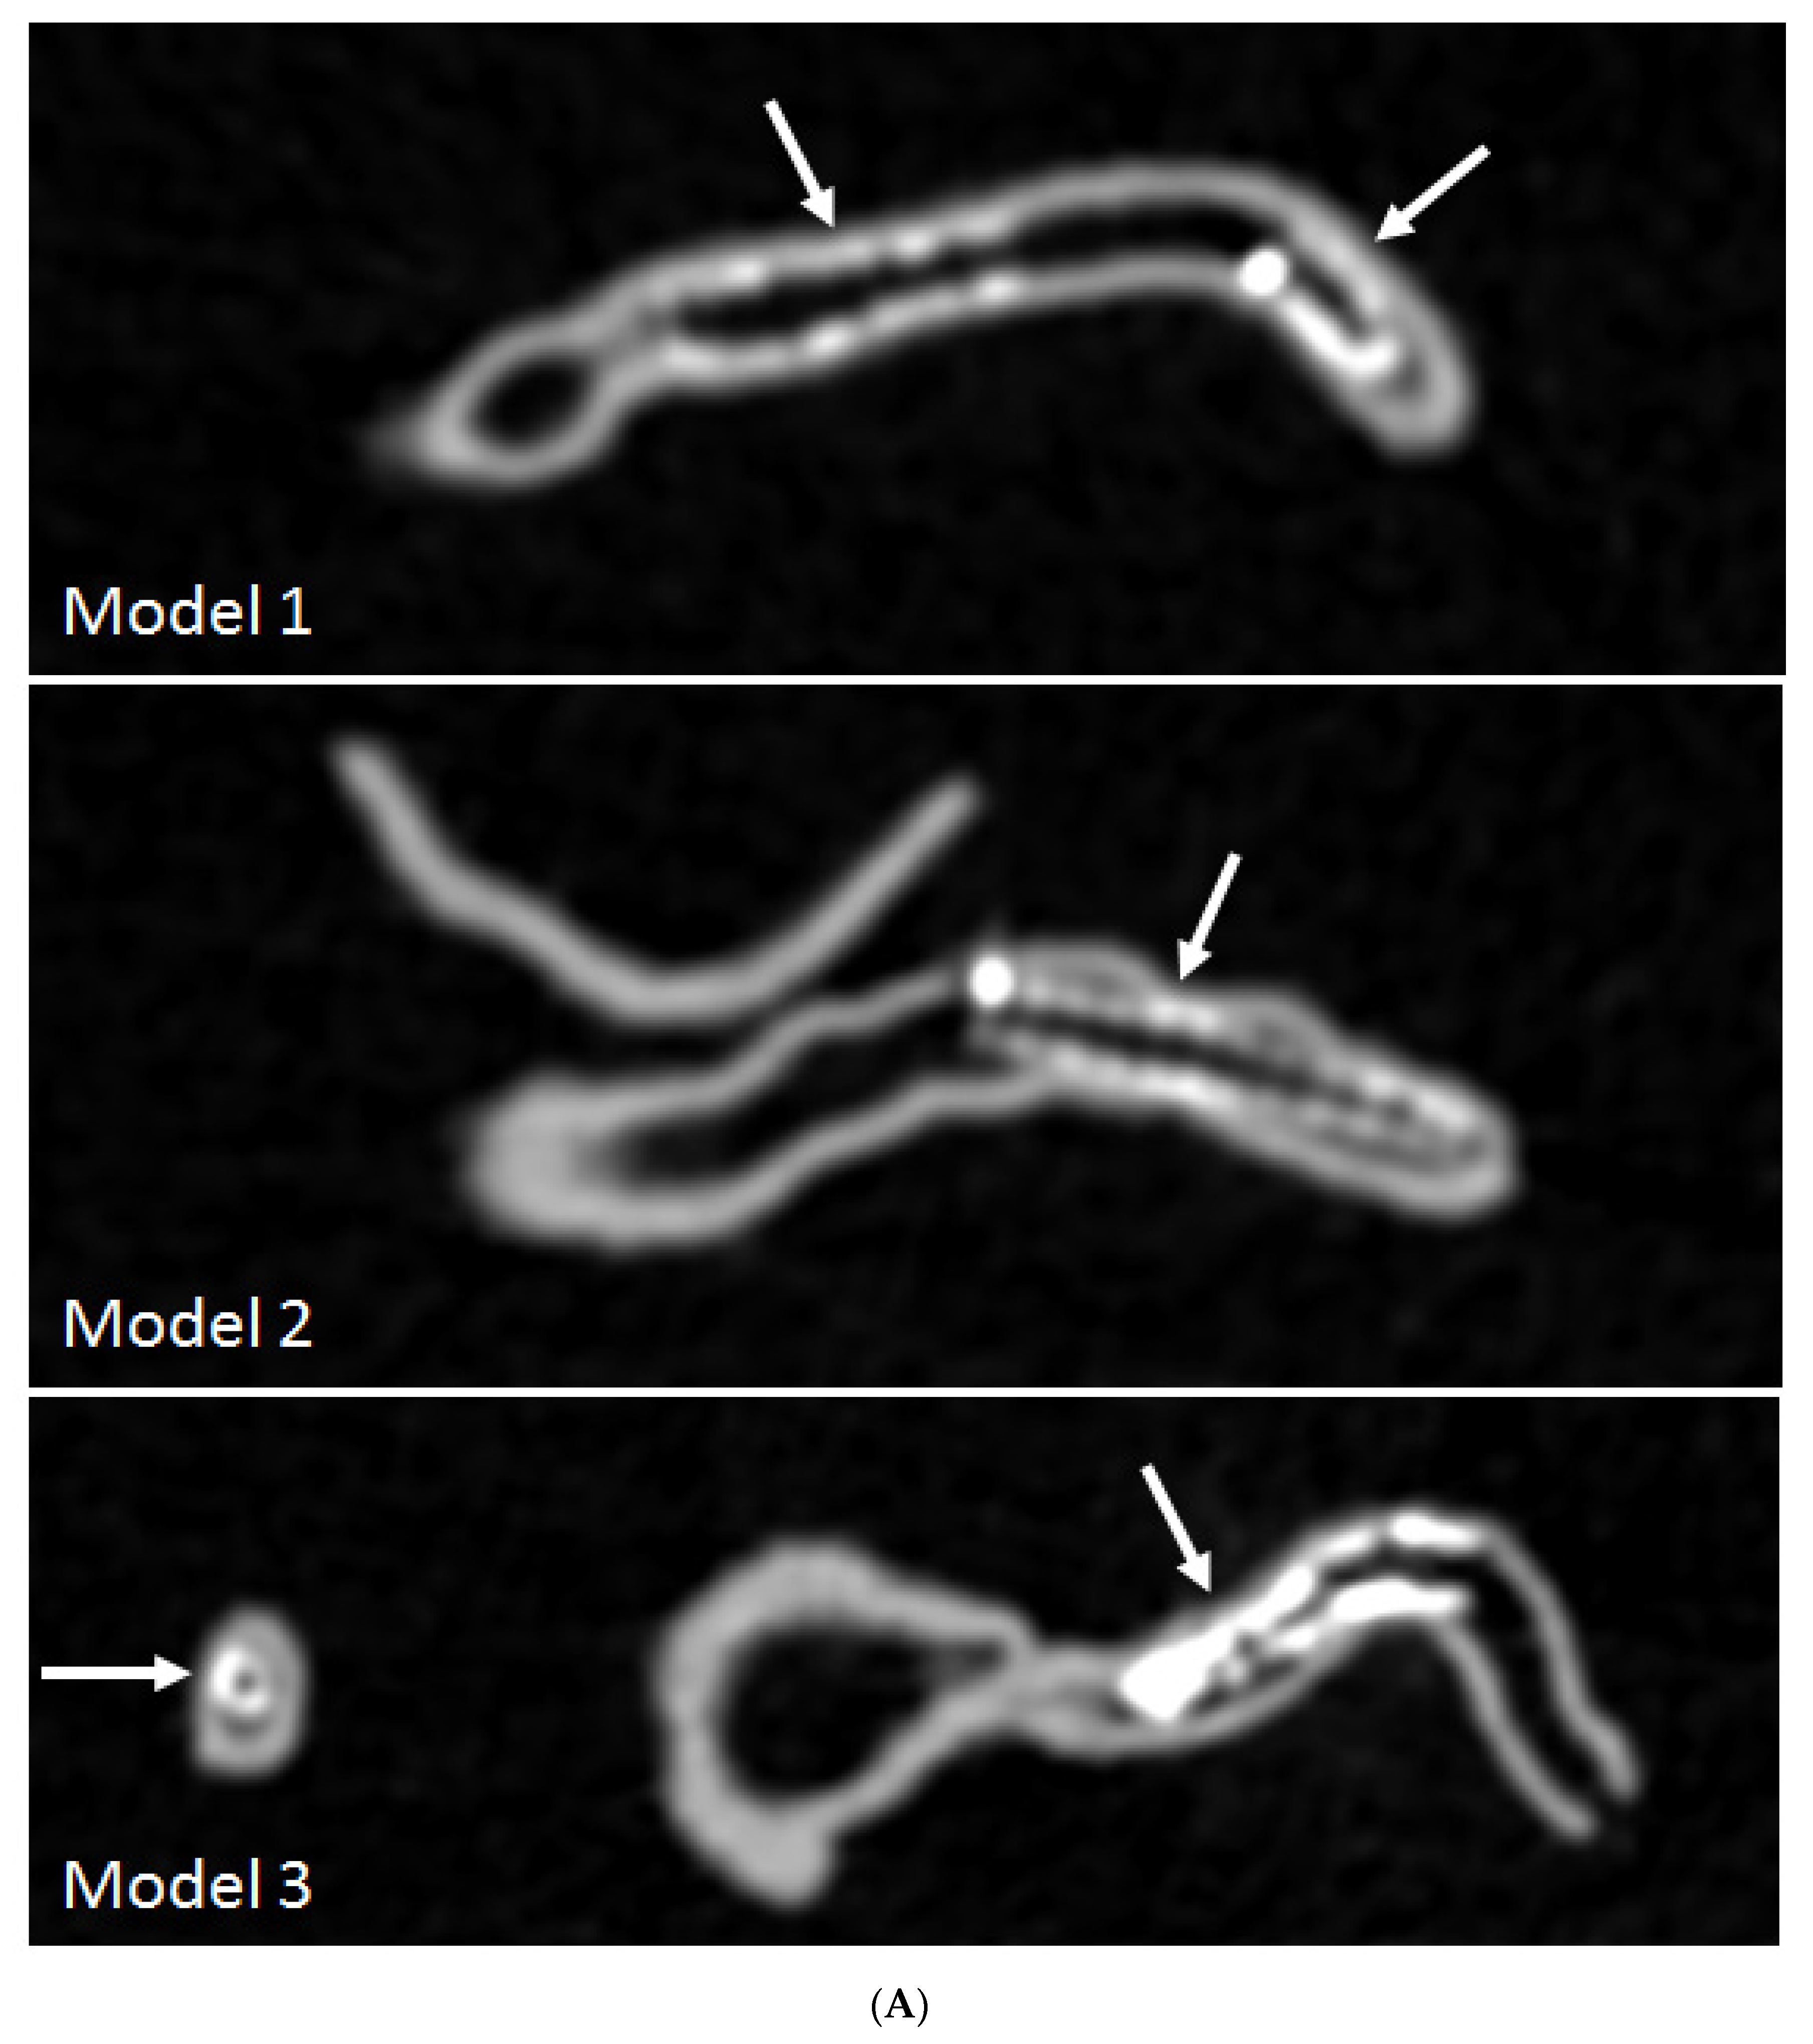

- Sun, Z.; Ng, C.K.; Squelch, A. Synchrotron radiation computed tomography assessment of calcified plaques and coronary stenosis with different slice thicknesses and beam energies on 3D printed coronary models. Quant. Imaging Med. Surg. 2019, 9, 6–22. [Google Scholar] [CrossRef] [PubMed]

- Sun, Z. 3D printed coronary models offer new opportunities for developing optimal coronary CT angiography protocols in imaging coronary stents. Quant. Imaging Med. Surg. 2019, 9, 1350–1355. [Google Scholar] [CrossRef] [PubMed]

- Sun, Z.; Jansen, S. Personalized 3D printed coronary models in coronary stenting. Quant. Imaging Med. Surg. 2019, 9, 1356–1367. [Google Scholar] [CrossRef] [PubMed]